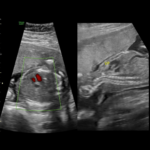

- Ecografía Prostática

- Ecografía Transvaginal